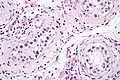

Intratubular germ cell neoplasia. H&E stain.

GCNIS is not palpable, and not visible on macroscopic examination of testicular tissue. Microscopic examination of affected testicular tissue most commonly shows germ cells with enlarged hyperchromatic nuclei with prominent nucleoli and clear cytoplasm. These cells are typically arranged along the basement membrane of the tubule, and mitotic figures are frequently seen. The sertoli cells are pushed toward the lumen by the neoplastic germ cells, and spermatogenesis is almost always absent in the affected tubules. Pagetoid spread of GCNIS into the rete testis is common. Immunostaining with placental alkaline phosphatase (PLAP) highlights GCNIS cell membranes in 95 percent of cases. OCT3/4 is a sensitive and specific nuclear stain of GCNIS.[3]